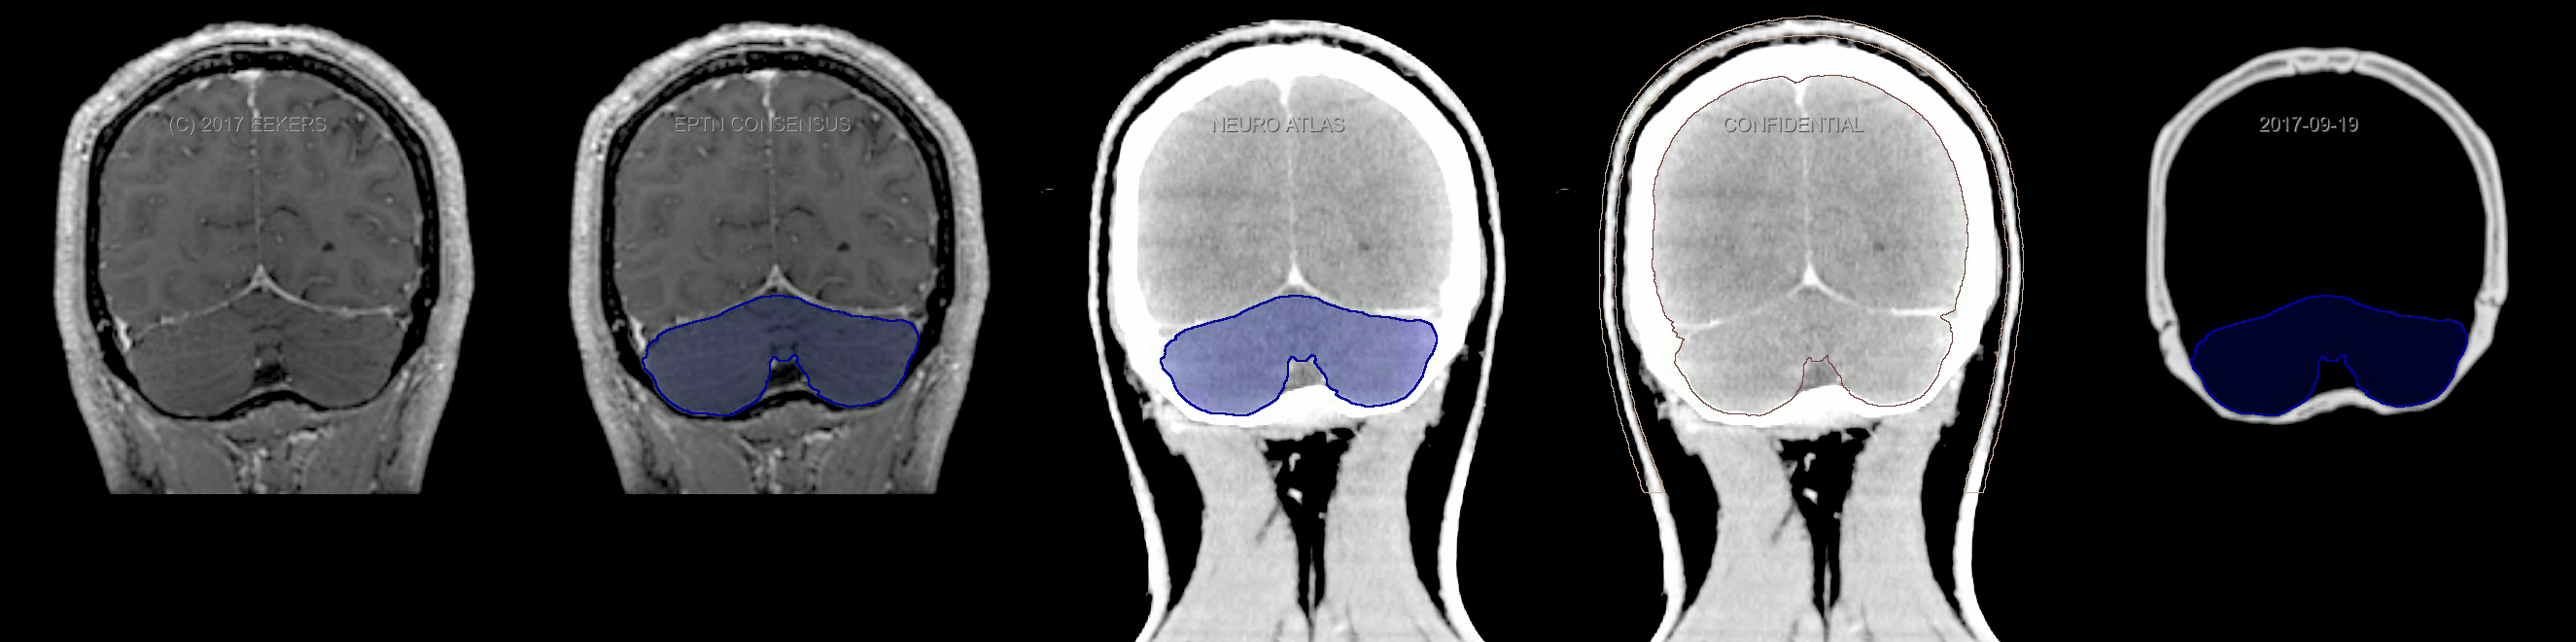

Eekers et al. have published an international neurological atlas for contouring of organs at risk in consensus with the European Particle Therapy Network (EPTN). The purpose of this consensus atlas is to decrease inter- and intra-observer variability in delineating OARs relevant for neuro-oncology. We propose this atlas is used in photon and particle therapy in order to derive consistent dosimetric data. When required this atlas will be updated according to new insights.

Included are all OARs known to be relevant for radiation-induced toxicity in neuro-oncology: brain, brainstem, cochlea, vestibulum & semicircular canals, cornea, lens, retina, lacrimal gland, optic nerve, chiasm, pituitary, hippocampus and skin. A new OAR relevant for neuro-cognition, the posterior cerebellum is also included.

Three-dimensional delineation of the fifteen consensus OARs for neuro-oncology are shown on CT and 3 Tesla (3T) MR images (slice thickness 1 mm with intravenous contrast agent). All are presented in transversal, sagittal and coronal view.

From left to right: MR without structures, MR with structures, CT (WW/WL 120/40) with structures, CT (WW/WL 120/40) with Brain and Brainstem Surface, CT (WW/WL 1500/120)with structures